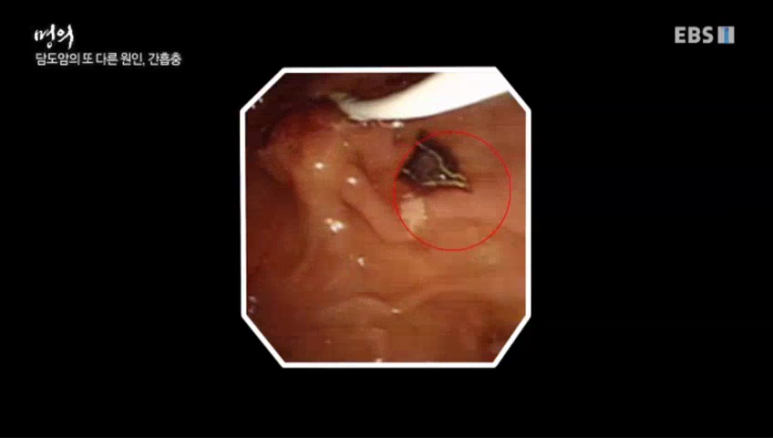

간디스토마로 불리는 간흡충은 민물고기를 날로 먹을 때 감염되는 기생충 중 하나다. 국민 100명 중 2명이 감염될 정도로 감염률이 높은 병이다.

민물고기를 날로 먹고 인체에 들어온 애벌레는 성충으로 자란 뒤 담도에서 장시간 기생해 알을 낳는다.

만약 1)간흡충의 성충이 담도 점막에 내려오면 담도 점막에 염증을 유발해 담석증과 같은 심한 통증을 유발한다. 또한 기생충을 앓으면 2)담도암의 원인이 되기 때문에 국제암연구기관에서는 간흡충을 1군 발암물질로 지정하고 있다. 따라서 간흡충이 있다면 종양검사도 함께 받아야 한다. 또 담석을 만들기도 한다.

사진에서 보이는 것이 간흡충이다 간흡충은 담도에 오래 기생하지만 길게는 2030년까지 기생한다.